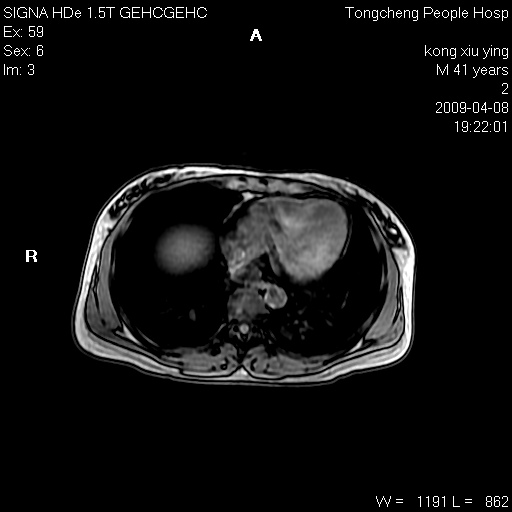

标题: CL1008:【经典】胆囊石榴籽样结石。 [打印本页]

标题: CL1008:【经典】胆囊石榴籽样结石。

女,41岁。健康体检——彩超提示:胆囊显示不清。平素健康,无不适感。

腹部mr扫描及mrcp,图像如下:

胆囊石榴籽样结石。